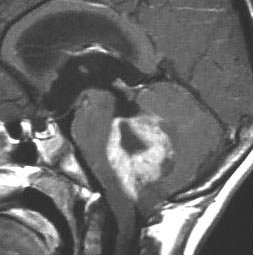

2歳の子どもにできたmedulloblastoma with extensive nodullarityのMRI CISS image矢状断層。多数の結節に分かれるこのタイプの髄芽腫は3歳未満の小児に発生し,化学療法によく反応します(右は1コースのICE化学療法後の顕著な縮小を示します)。従って,classical medulloblastomaよりも予後が良いといえます。リスクを侵して全摘出する必要はなく,また幼児発生であることも考慮すれば放射線治療の intensityも高く設定する必要はないのかもしれません。同じ3歳未満のhigh-risk groupの髄芽腫といえども,2歳児のanaplastic medulloblastomaとは治療反応性に天地の開きがあります。